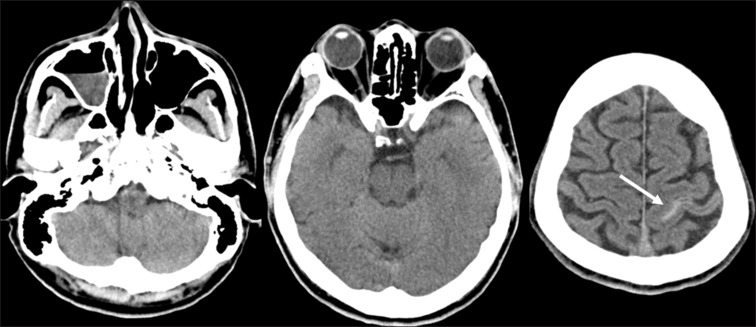

Subarachnoid Hemorrhaging Occurring during Drowning.

溺水时发生的蛛网膜下腔出血。